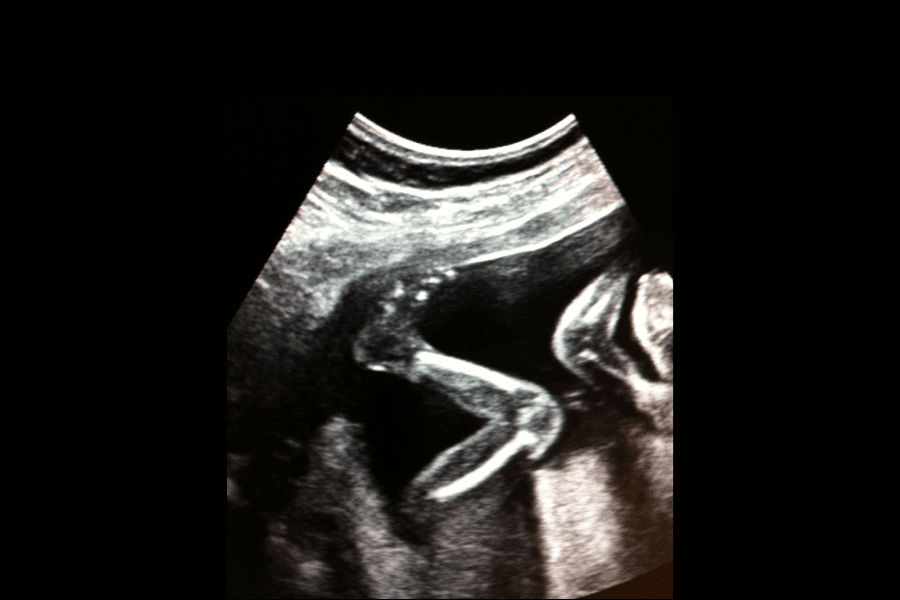

Come il feto si muove all’interno della pancia è molto individuale, atteso che il grado di mobilità di ogni bambino varia in base alla personalità ed alla situazione. Il bambino inoltre compie dei movimenti molto piccoli che sono difficili od impossibili da percepire. Il bambino scalcia, si esercita nell'arte respiratoria e ad ingoiare, oltre ad allenare i propri riflessi di prensione e suzione. Non si tratta sempre di calci.

Il modo in cui la gestante percepisce i movimenti fetali dipende dalla personalità del bambino, dallo spazio a sua disposizione, dalla posizione assunta dal bambino all’interno dell’utero e dalla posizione della placenta.